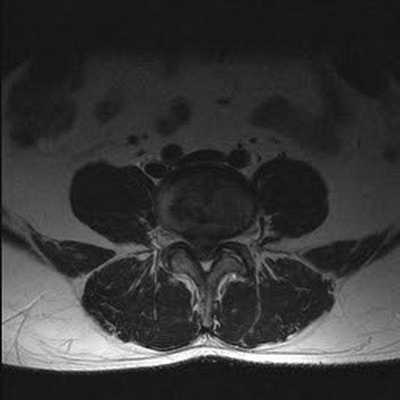

МРТ позвоночника. Т2-взвешенная МРТ, срез через межпозвоночное отверстие. Красные стрелки - корешки. Межпозвоночное отверстие обведено малиновым. P- ножка дуги. VB - тело позвонка.

МРТ позвоночника. Аксиальная Т2-взвешенная МРТ. Нормальный срез через дугоотростчатые суставы.